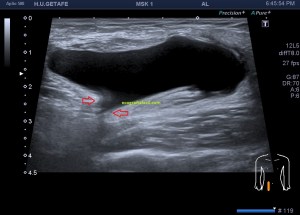

1

En la imagen 1 observamos la rotura en eje corto, mas flechas rojas señalan el músculo dañado, las amarillas la rotura en si. Observamos la anatomía que la rodea y que es referencia siempre.